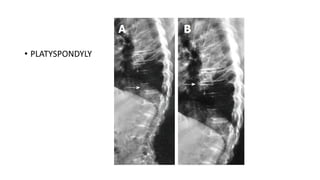

• PLATYSPONDYLY

• Severe platyspondyly with narrow disc spaces